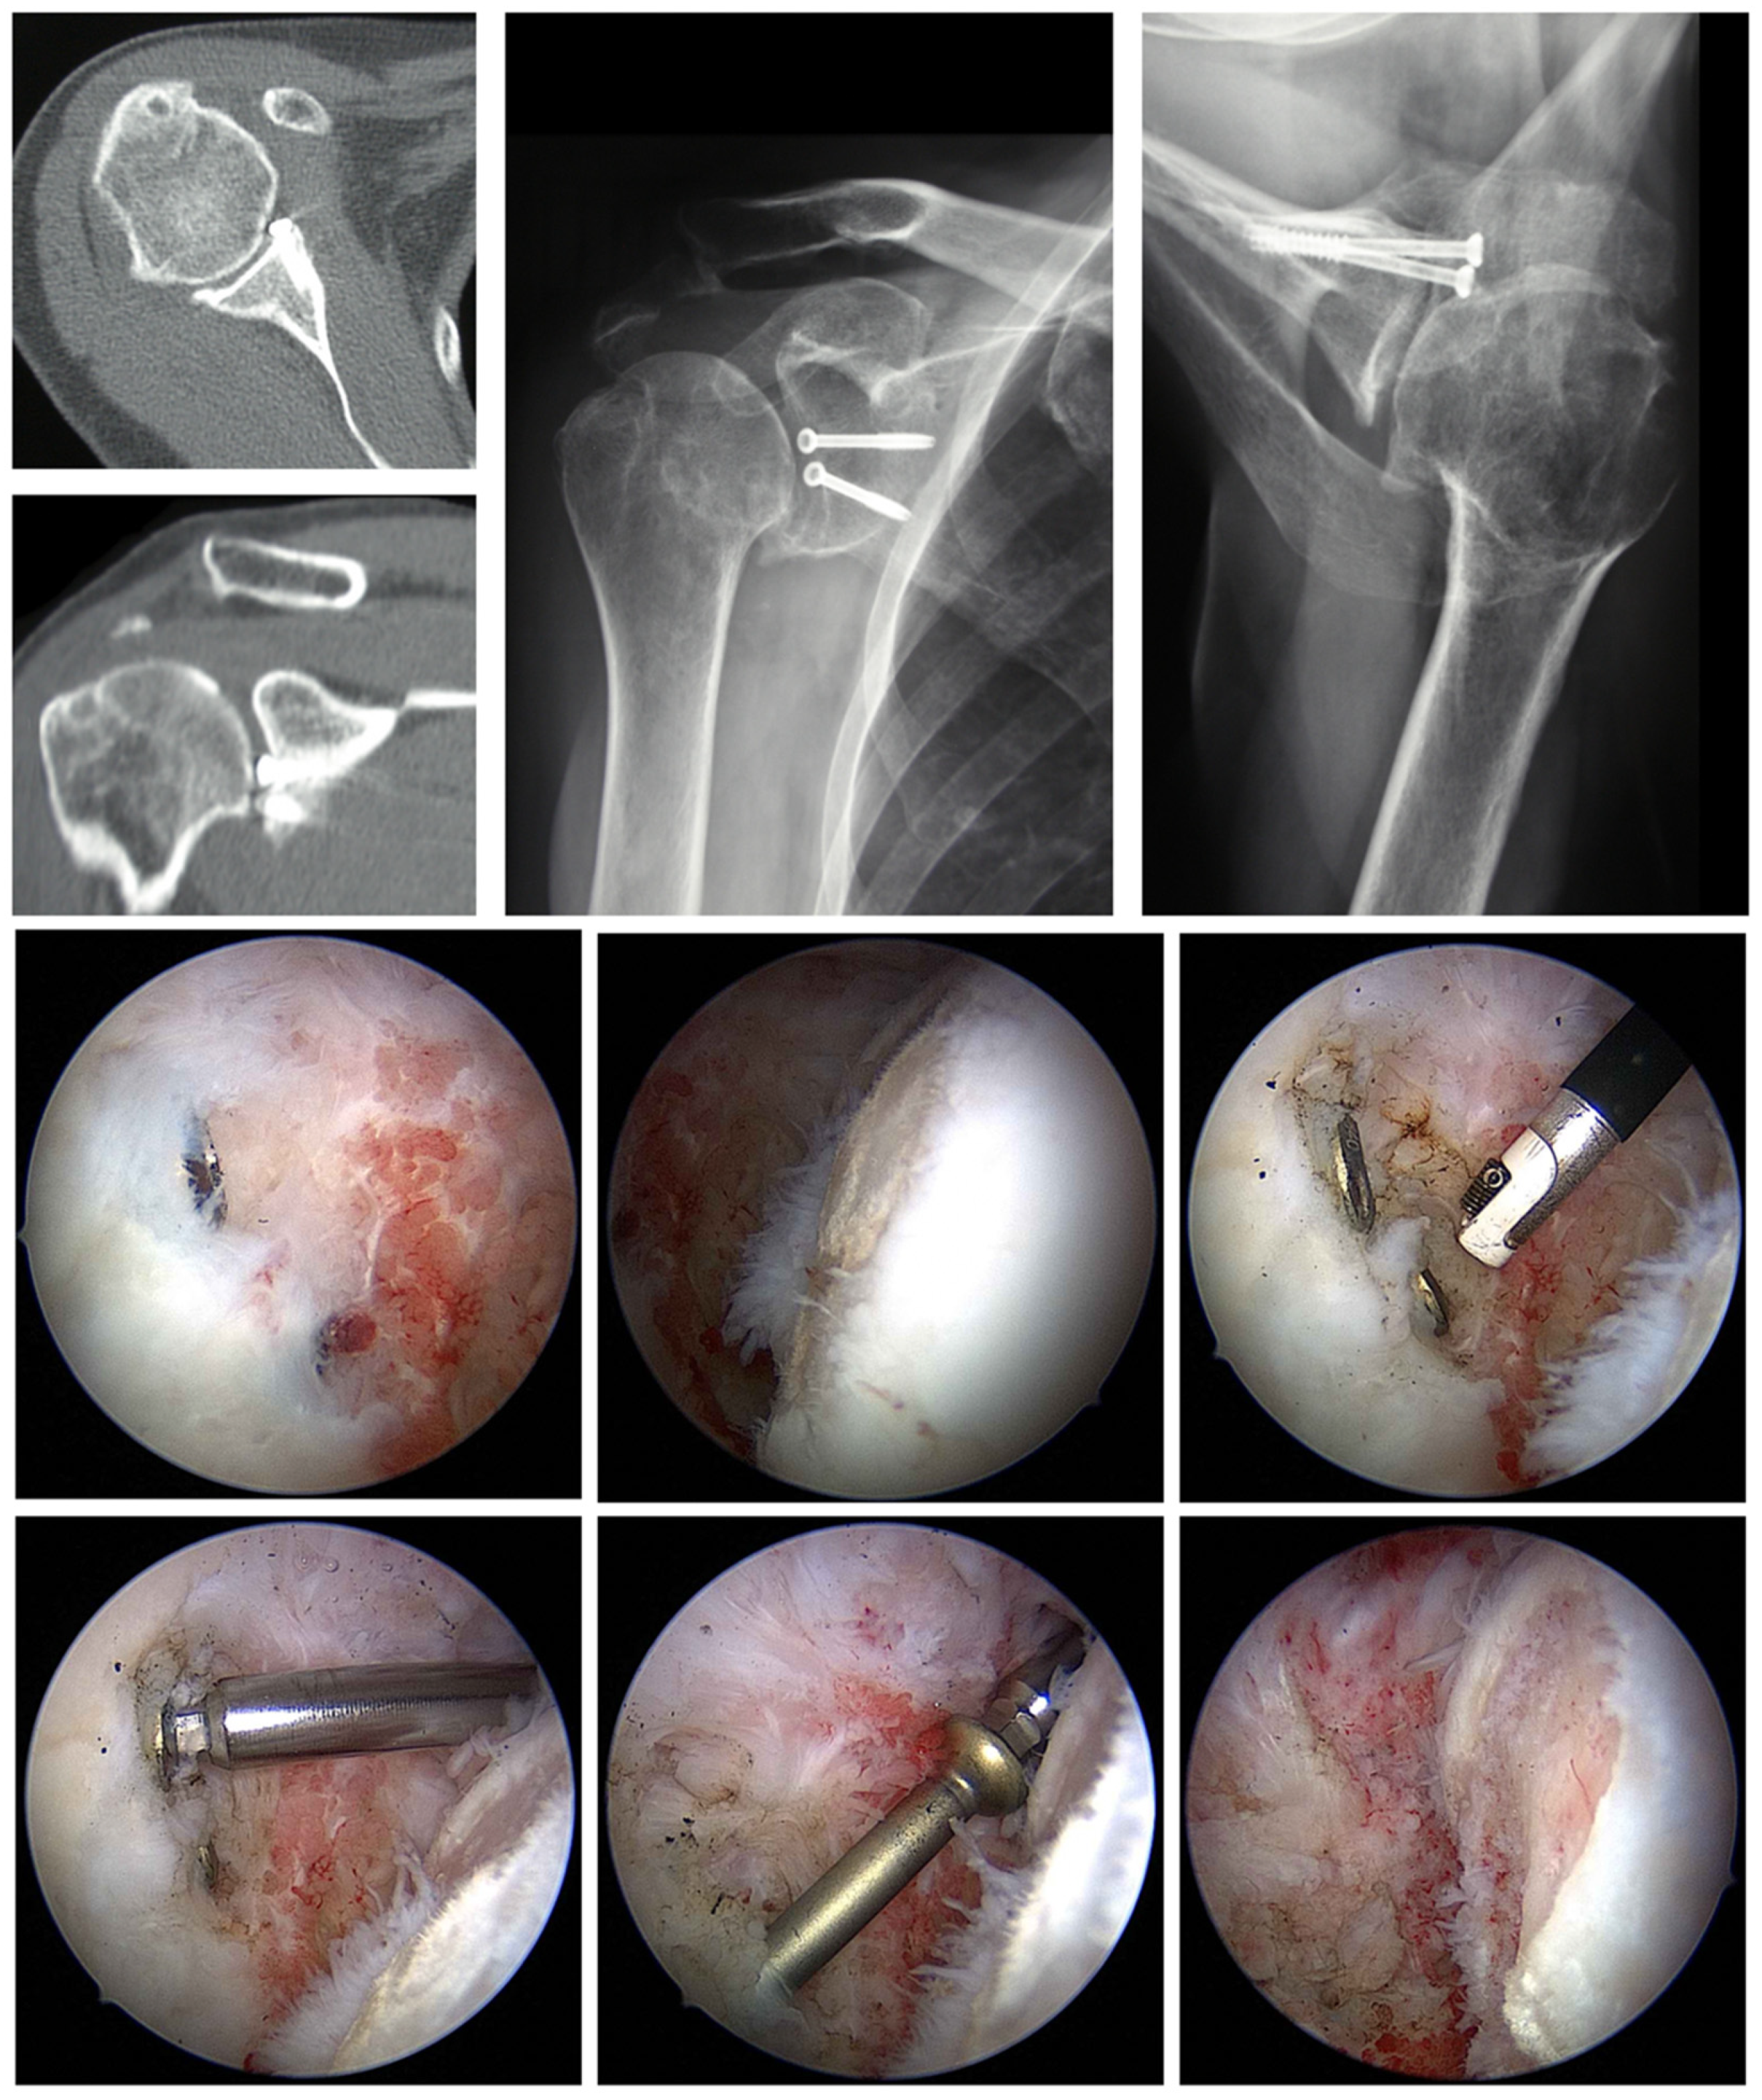

- Tauber, M.; Moursy, M.; Eppel, M.; Koller, H.; Resch, H. Arthroscopic Screw Fixation of Large Anterior Glenoid Fractures. Knee Surg. Sports Traumatol. Arthrosc. 2008, 16, 326–332. [Google Scholar] [CrossRef]

6.2. Removal of Foreign Material

6.3. Arthroscopic Debridement and Arthrolysis